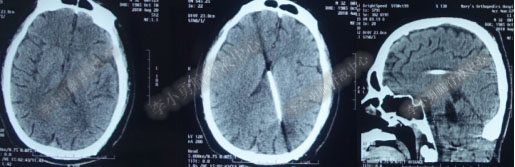

第4次出院后11天即2018年4月15日(分流术后284天,第2次的软性内镜术后179天),因引流管堵塞第5次住入该院,引流管内白色絮状物增多,引流管被堵塞。入院当天复查头部CT(图-10)显示脑室系统仍扩张。

图-10:2018年4月15日头部CT

第5次入院第2天即2018年4月17日,脑室腹壁外引流管堵塞,意识恶化,复查头部CT(图-11)示全脑室系统又较前扩大。当天急诊行左侧脑室穿刺外引流术。脑脊液化验外观黄色浑浊,并且送培养,结果是无菌生长。

图-11:2018年4月17日头部CT脑室扩张又加重

第5次入院第3天即2018年4月18日术后复查头部CT(图-12)显示脑室系统扩张较前好转。

图-12:2018年4月18日头部CT